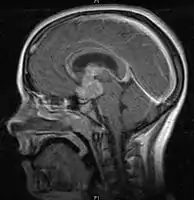

- Mainly located in midline structures, suprasellar region or pineal gland, also basal ganglia and hypothalamus

- Pineal Gland Germinoma

- Suprasellar Germinoma

- Toronto; 2006 (1995-2004) PMID 16530340 -- "Limited-field radiation for bifocal germinoma." (Lafay-Cousin L, Int J Radiat Oncol Biol Phys. 2006 Jun 1;65(2):486-92.)

- Retrospective. 6 patients with bifocal germinoma (pineal + suprasellar). All with diabetes insipidus at presentation. Treated with chemo followed by limited-field RT (whole ventricle 24-40 Gy +/- boost). Median F/U 4 years

- Conclusion: Bifocal germinoma can be considered locoregional rather than metastatic disease